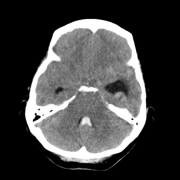

海绵状血管瘤是一种血管畸形,占颅内血管畸形的颅内症状性海绵状血管瘤发生于脑干。脑干海绵状血管瘤的自然史尚不清楚,一旦有症状,其临床进展很...

虽然脑干海绵状血管畸形一度被认为不能手术治疗,但在病人选择、手术暴露、术中MRI引导、MR纤维束成像和神经生理学监测等方面的改进已使大多数手术...